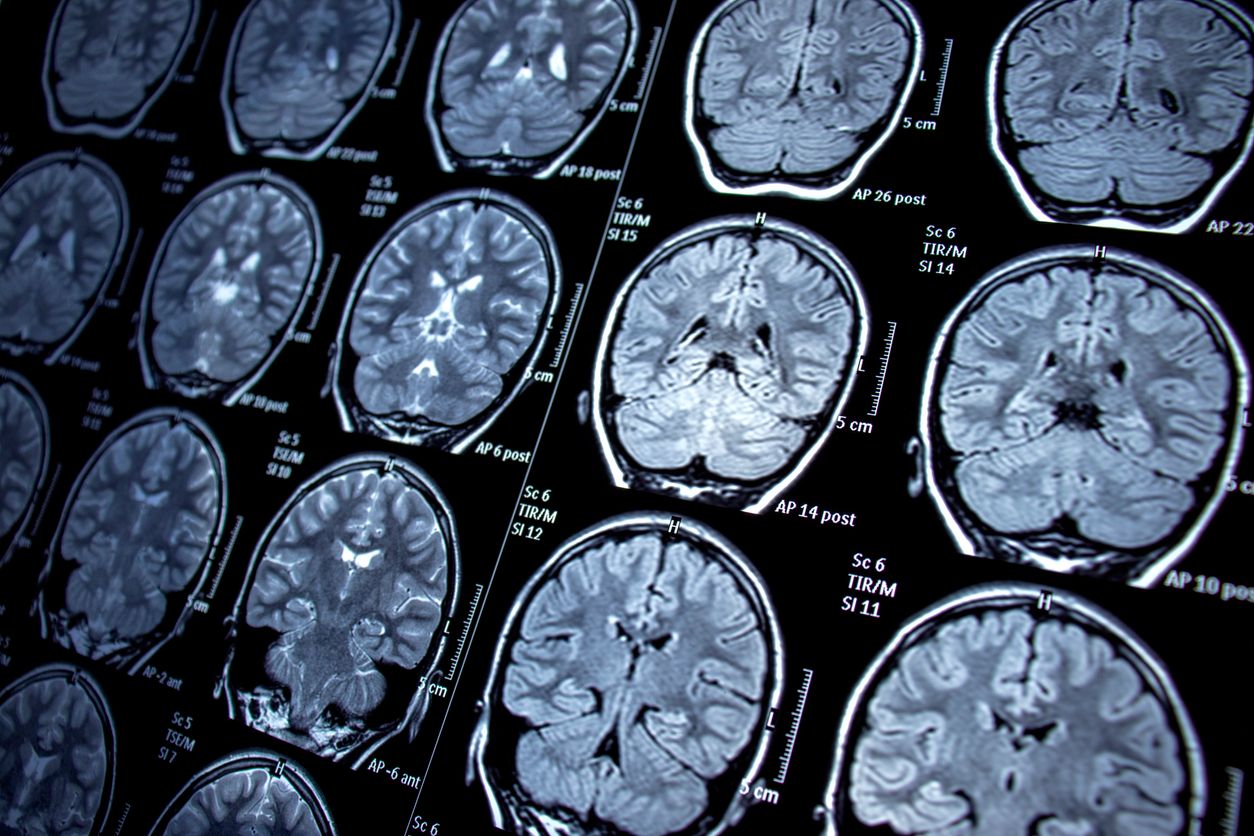

Wenig Gewebe mit großer Wirkung: Die Amygdala.